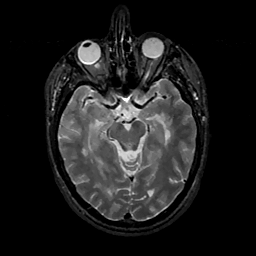

MR Study #11, May 5, 1991 -- Slice #20